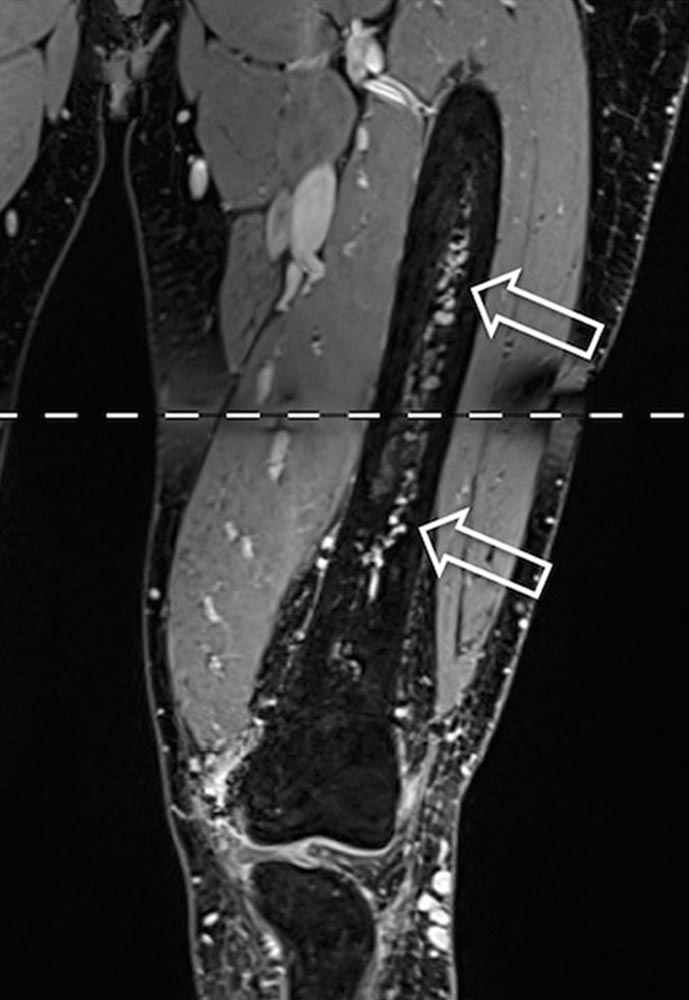

Owing to the presence of shunts, this swelling may be associated with pulsation and increasing, spreading warmth. As a result of the increased volume and pressure load in the venous system, symptoms of chronic venous insufficiency may ensue. Both venous insufficiency and reduced arterial blood flow peripheral to the nidus can lead to a diffuse spread of pain. Compression or invasion of the surrounding tissue, caused by shunts and dilated vessels, can additionally cause functional and movement restrictions (e.g., muscle contractures, joint or bone involvement).

• Locomotor system: muscle contracture, arthrosis, difference in leg length, hyperplasia of a limb